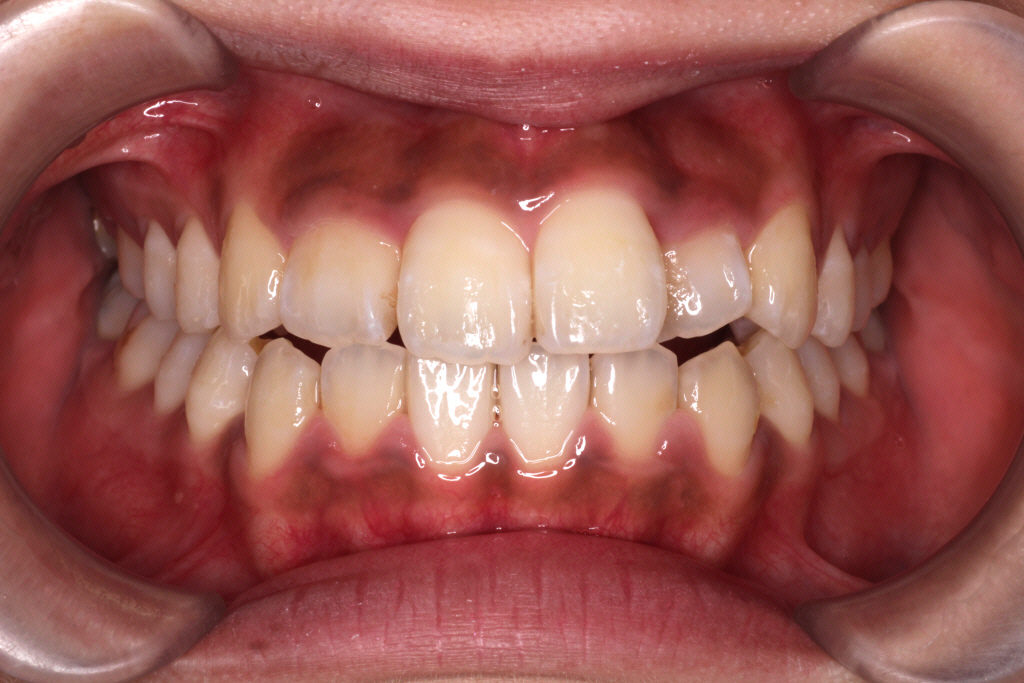

6ヶ月後、今回はだいぶ並んできました。↓

●改善点の結果

① 左上の2番目の歯は歯列に入りましたが、まだ少しねじれています。

② 右上の2番目の歯の切端咬合が、下の歯より上の歯が前方に出て、正常になりました。

③ 側方の噛み合わせが上1本に対して、下2本になりました。きれいに改善されました。

④ 噛み合わせがよくなり隙間がなくなりました。こちらも改善されました。

②~④の症状は解決したので、あとは①を改善するようにリファイメント3回目を行います。